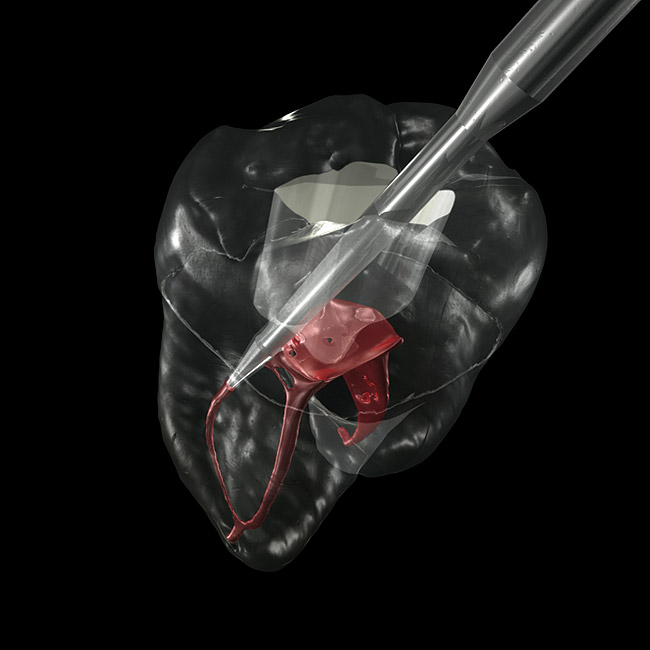

When a machined, smooth, and conical-shaped preparation is cut with conical carbide, the visual contrast between dentin and pulp tissue remnants (PTRs) is visually apparent and tactilely accessible ( Figure 12). Microsurgeon dentists operating at 8x to 24x magnification with an operating microscope can leverage the optimized dentinal maps for direct visual recognition of tiny PTR s, even when the smallest hand file does not bind. Endodontists and dentists who elect to perform endodontics without microscopes benefit from the tactile advantage of the conical shape. In either case, the patient can benefit, because minimized gouging allows peri-cervical dentin (PCD) to be maintained. PCD is defined as the crucial dentin in the "neck of the tooth," from 4 mm coronal to crestal bone to 4 mm apical to crestal bone.

The feature case of this article, highlighted in Figure 13 through Figure 24, demonstrates a comprehensive shift in many aspects of endodontic access. The calcified central incisor ( Figure 13) of a 42-year-old woman was treatment planned for elective endodontics to facilitate internal bleaching for esthetic reasons. The preoperative radiograph demonstrated almost complete obliteration of the pulp, except for a small pouch in the center of the root. Referring these challenging cases to a microscopeequipped endodontist should always be considered. However, many well-trained general dentists attempt these difficult cases, and most dentists routinely deal with partially calcified cases. Still, the concepts forwarded in this case can be employed as indicated in every endodontic access treatment.

The first step in the access for the calcified tooth is the establishment of the palatal–incisal notch ( Figure 15 and Figure 16). Once the area where the original pulp chamber was located has been accessed, it is advisable to take an orientation verification radiograph or multiple angled radiographs ( Figure 17). The palatal–incisal notch works in concert with the narrow shaft of the bur to perform important tasks. Similar to a surgical stint for implant drilling, the notch first stabilizes and directs the head of the bur by cradling the shaft. Secondly, it allows a more appropriate angulation—toward the incisal—of the back of the bur. Anatomy lessons have taught clinicians that the root and the crown of incisors are not parallel.

The resultant cavosurface outline is quite long and fairly narrow for the calcified tooth, and creates better potential for accuracy ( Figure 18 and Figure 19). A final view of the access in Figure 20 shows the orientation of the palatal–incisal notch and the dentinal map, which is encountered as early as possible. The radiographic sequence ( Figure 21, Figure 22, Figure 23 and Figure 24) teaches a new concept in accessing calcified canals, that of radiographs taken using the pointing quality of a conical bur to assess direction and position of the access cavity. Corrective steps can then be taken to avoid gouging or perforation. In the past, only endodontic files have been used as metallic (radiopaque) radiographic markers. The snug fit of a conical bur as opposed to the loose fit of a round bur facilitates the use of the bur in taking "bur instrument films."